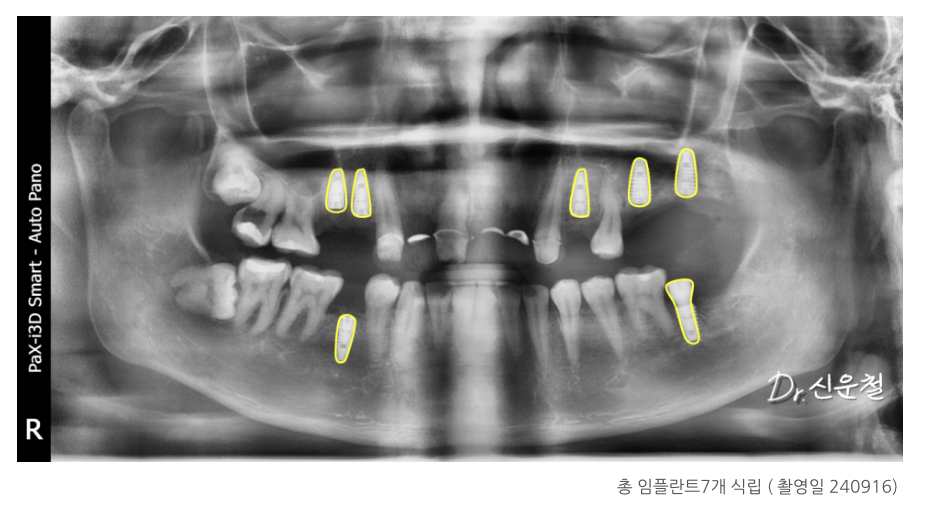

3차 치료: 임플란트 7개 단계적 식립